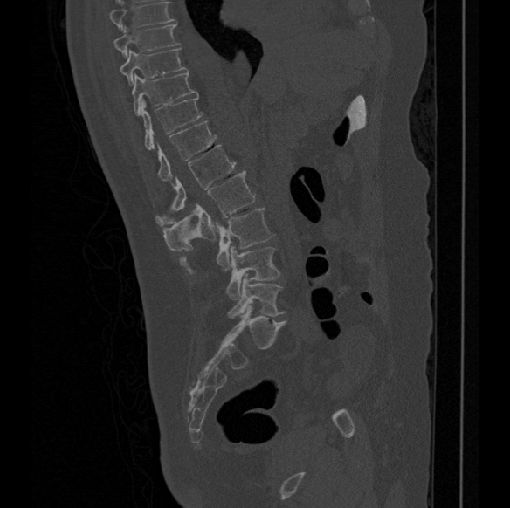

Spinal imaging via computed tomography (CT), magnetic resonance imaging (MRI), radiography, ultrasound, positron emission tomography (PET), and other radiologic imaging modalities is essential for noninvasively visualizing and assessing spinal pathology. Computational methods support and enhance a physician’s ability to utilize these imaging techniques for diagnosis, noninvasive treatment, and intervention in clinical practice. Analysis algorithms developed in the field of computer vision, computer graphics, signal processing, and machine learning have been adapted to analyze spinal images (Li et al., 2015). Conventionally, CT is preferred to study the spine due to a high bone-soft tissue contrast. There are diverse image appearance variations due to differences in vertebral position, metal artifacts and spinal diseases, etc., challenging the analysis algorithms. Fig. 1 gives some examples of these various conditions.

We calculate the two metrics of each vertebra, and the results are reported in Table 2. On the one hand, our experimental results are close to those reported in reference (Sekuboyina et al., 2020) with the same model (nnUnet), verifying the high quality of our annotations. On the other hand, Table 2 shows it is difficult to segment the diseased vertebrae (the DSC of L6 is almost 0). Specifically, the existence of L6 confuses the model, resulting in prediction dislocations (see the last row in Fig. 4). Thus, our labeled dataset, which contains many L6 cases, is very valuable for the diseased vertebrae segmentation (we have stated those cases that are hard for annotation in the readme.txt file). Table 2 illustrates that the model trained with our annotations can achieve good performance on our CTSpine1K dataset but a much worse performance on the VerSe Challenge datasets, which explains there is an obvious domain gap between our annotated dataset and the public dataset. We infer the reason is that the COlONOG dataset is based on an empty stomach and colon, confusing the deep learning model by the changes of air content in the abdomen (see Fig. 3). Therefore, our annotations are a good complement to the existing datasets.

Some visualization results are presented in Fig. 4, where we can observe that the baseline model can achieve excellent segmentation results. Nevertheless, some failed predictions occur when spinal diseases exist, especially sacral lumbarization and lumbar sacralization. Besides, the image’s resolution of Z direction is closely related to the results, and a lower resolution leads to worse results. Maintaining a reasonable performance for a low resolution is a research challenge. Image superresolution (Peng et al., 2020) might be worth exploring.